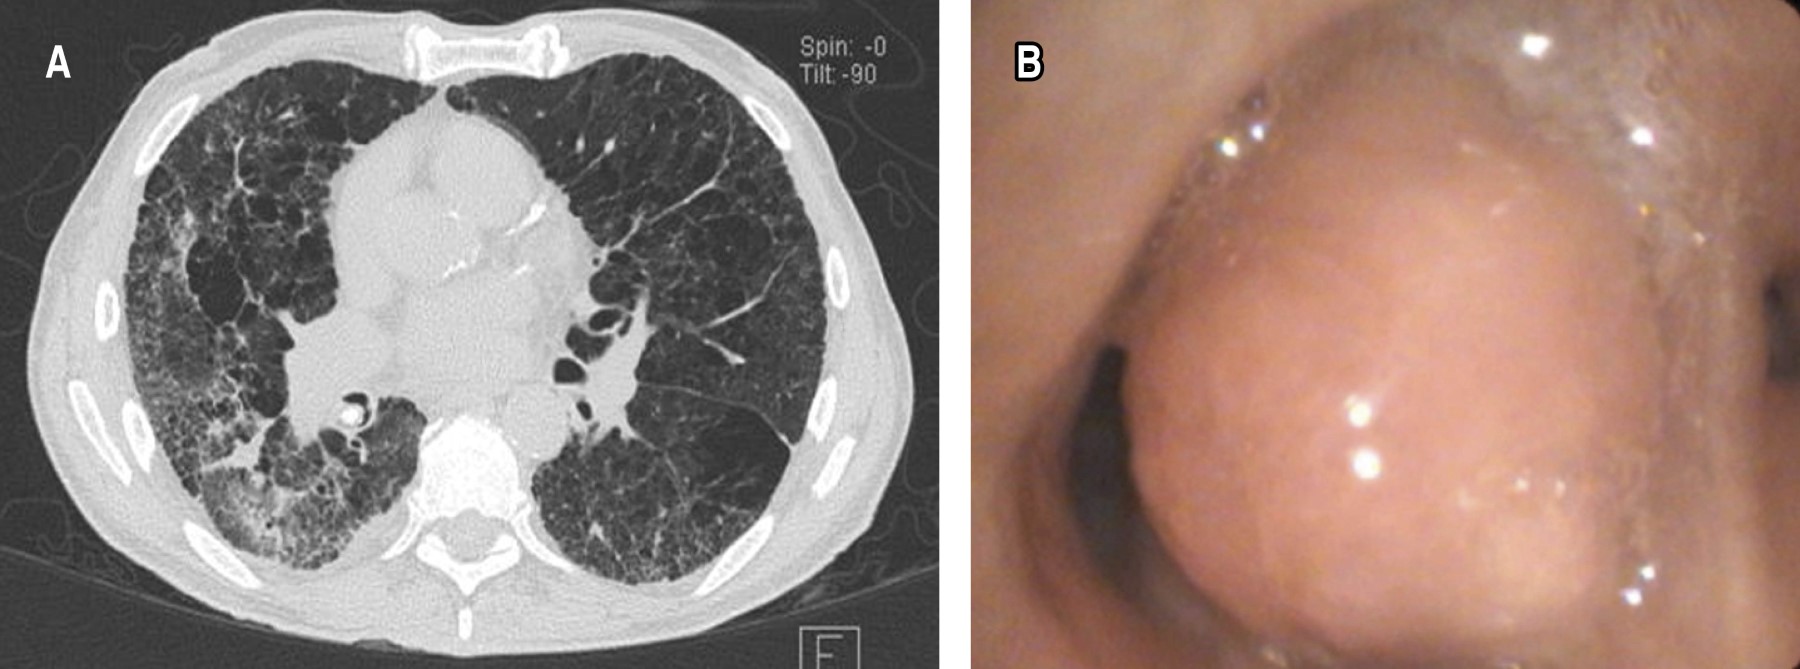

Sixty-four endobronchial tumors were identified, the most frequent location was in the right bronchial tree, with 39 (60.9%) patients. Of these, 19 (29.6%) were found between segments 6 to 10 right, 12 (18.7%) in the middle lobe and eight (12.5%) in segments 1 to 3. In the left bronchial tree, 25 cases (39%) were observed. Of these, six (9.3%) were found between left segments 6 to 10, 10 (15.6%) in the lingula and nine (14%) in segments 1 to 3 (Figures 1 and 2).

Contrast-enhanced computed tomography was also crucial in the evaluation of suspicious lung lesions, providing more precise anatomical details. Tumor lesions were identified in 66.7% of patients and hilar and prebronchial lymphadenopathy was observed in 68.8%, which highlights the importance of this technique in the evaluation prior to more invasive procedures such as bronchoscopy.5

Regarding the diagnostic tools available today, it is essential to highlight the importance of advanced technologies in bronchoscopy, such as narrow band imaging (NBI), bronchial autofluorescence (BAF) and high-magnification bronchoscopy. These modalities allow detailed visualization of mucosal and vascular lesions, facilitating the detection of suspicious high-grade lesions. NBI, for example, uses blue and green light to highlight the vascularization and structure of the mucosa, improving the identification of areas of dysplasia and neoplasia at early stages.7,8